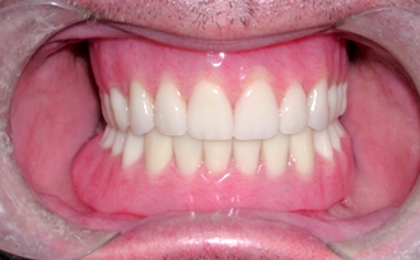

自分の歯に近い咬み心地と自然な見た目を

インプラント治療とは、外科手術でインプラント(人工歯根)を顎の骨に埋め込み、その上にセラミック製の人工歯や特殊な入れ歯を装着して歯の機能を補う治療法です。チタン製で形状や加工に工夫を施した人工歯根が顎の骨にしっかり固定するので、自分の歯に近い力で咬むことができます。セラミック製などの被せ物を装着すれば自然な見た目に仕上げることができ、発音にも食事にもほとんど支障がありません。そのため他人に治療をしたことを気づかれずに済みます。

メリット

• 硬い物でもしっかり咬めます

• 天然歯のような自然な仕上がりになります

• まわりの歯に負担をかけません

• 咀嚼の刺激が伝わるので顎の骨が痩せにくくなります

• 適切なメンテナンスにより長期使用が可能です

• 周りの歯を削らないで済む